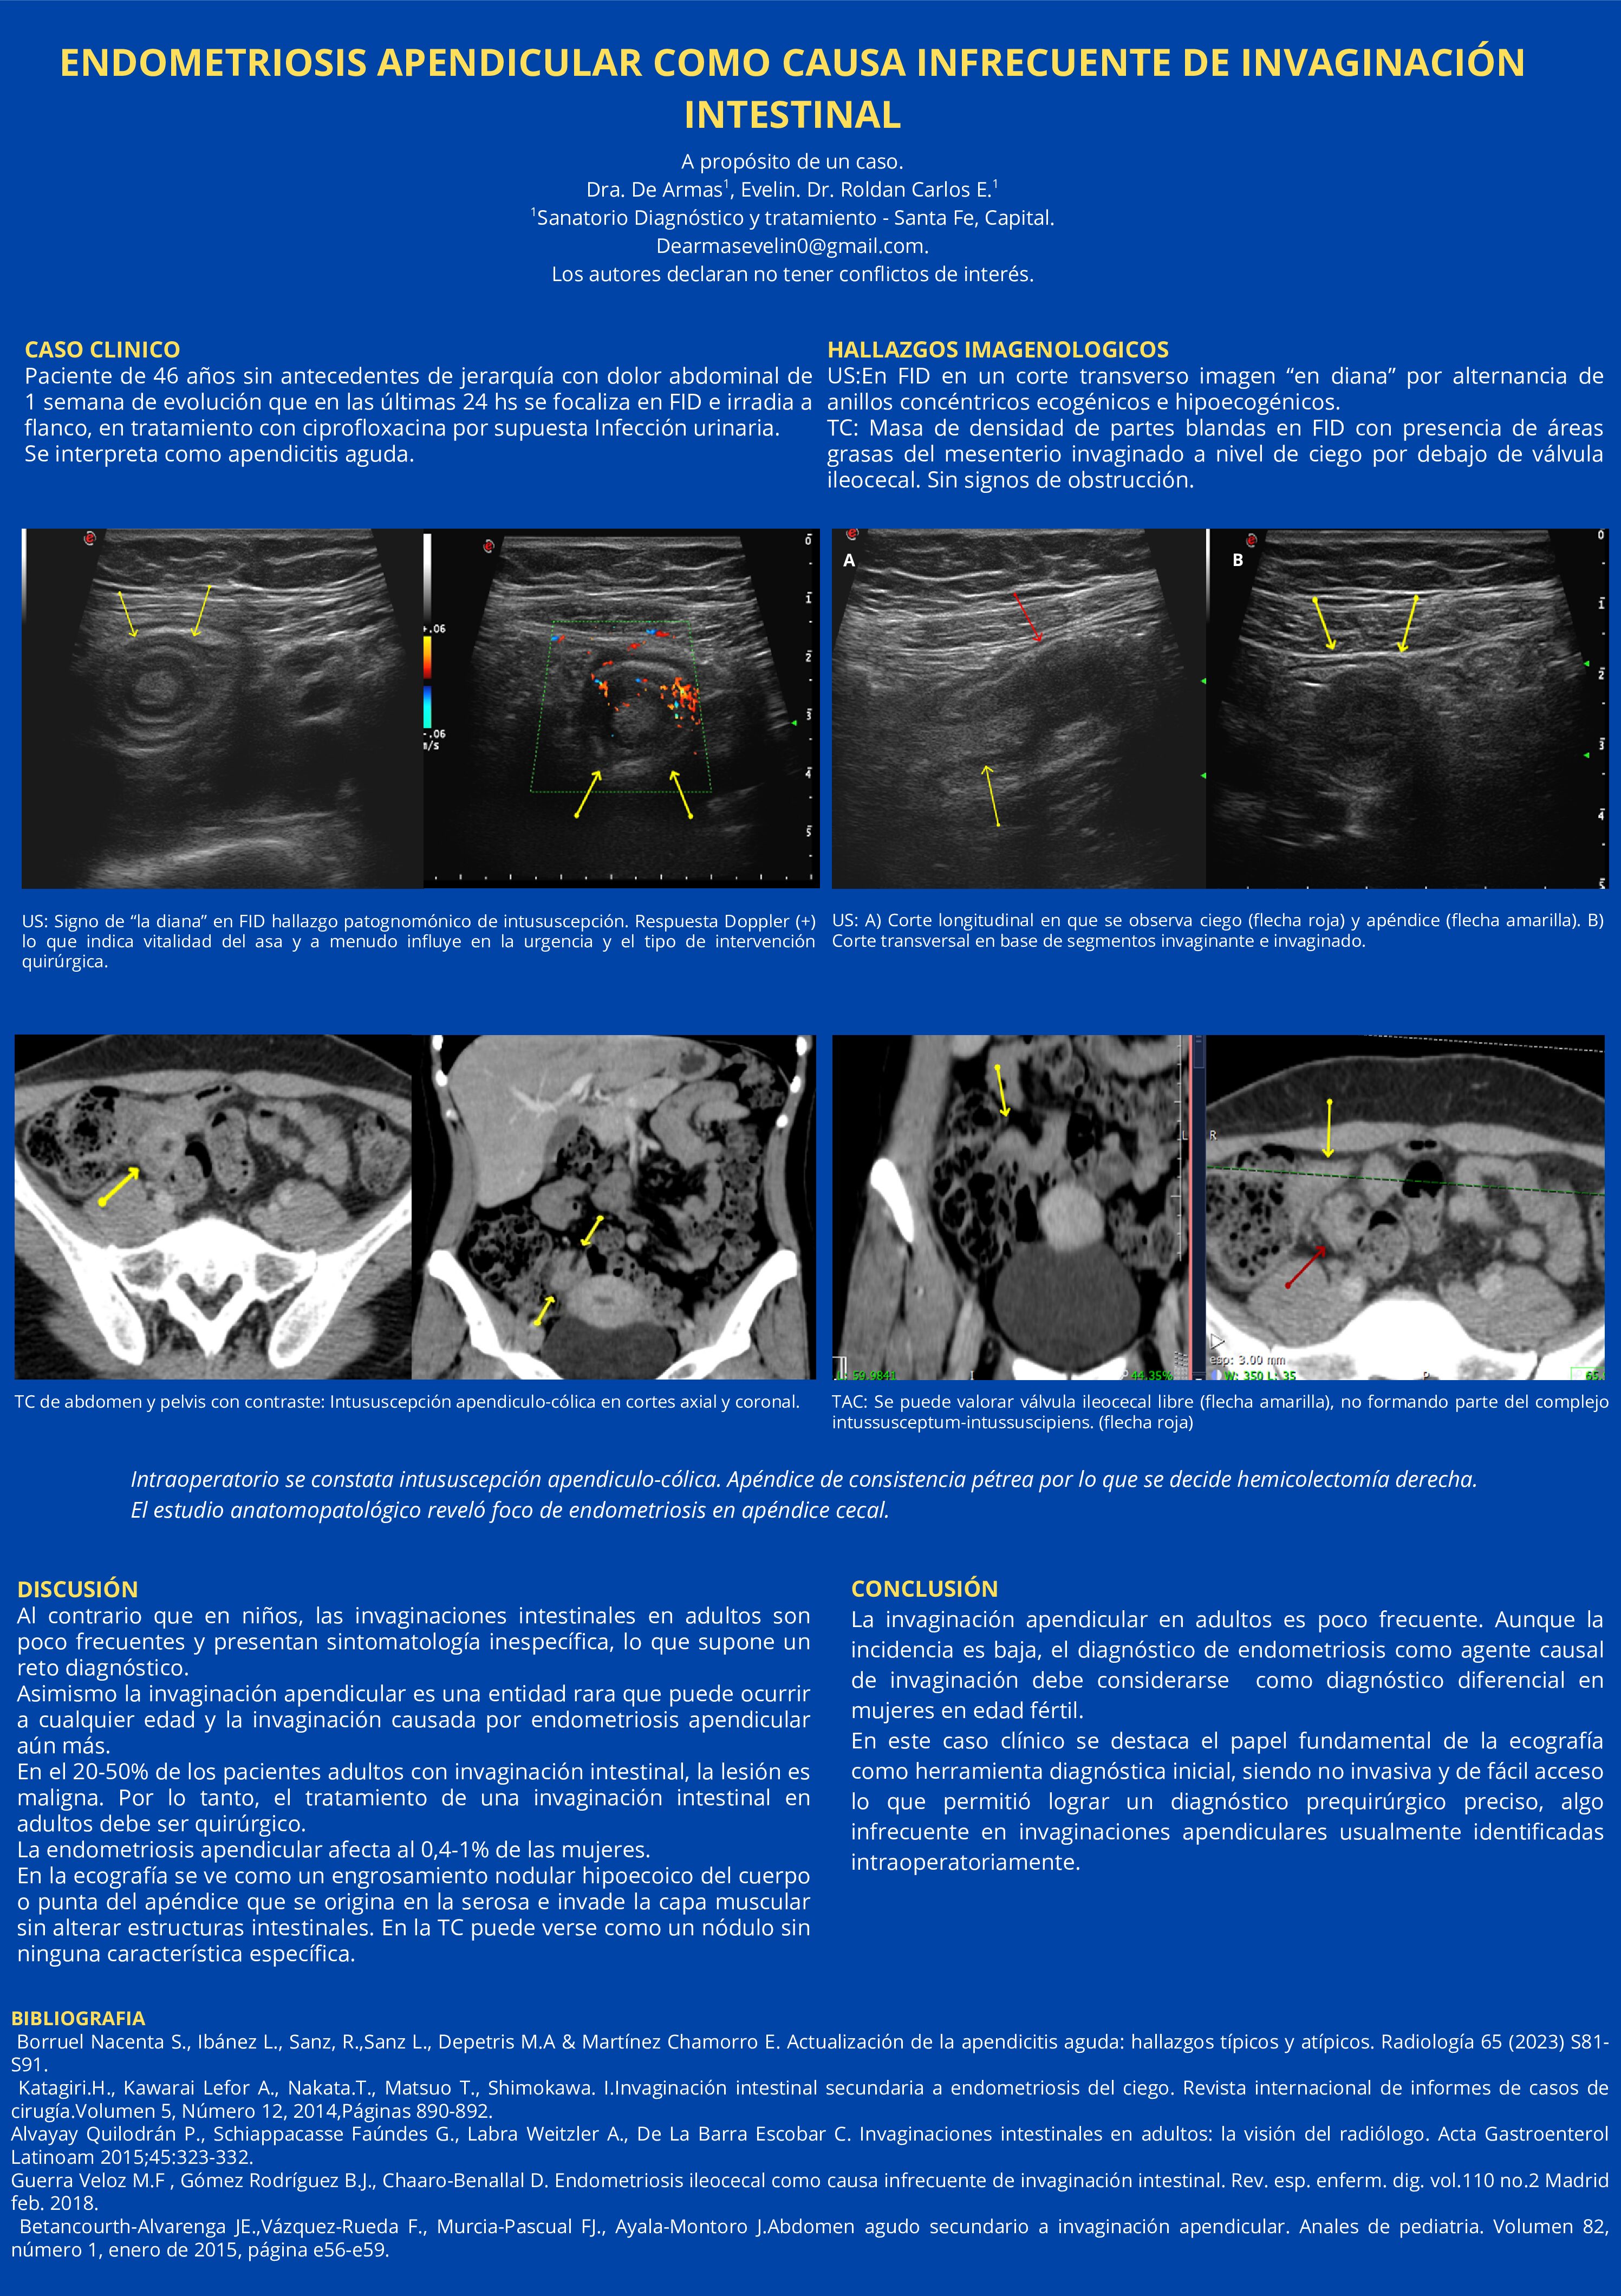

ENDOMETRIOSIS APENDICULAR COMO CAUSA INFRECUENTE DE INVAGINACIÓN INTESTINAL

07/07/2025